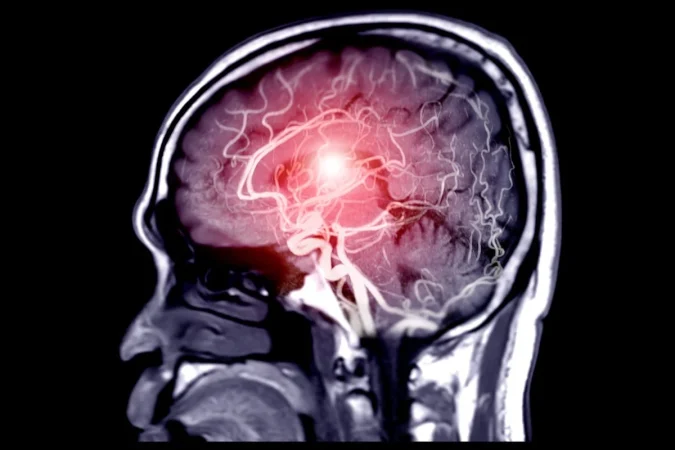

En el marco del mes dedicado a crear conciencia sobre el aneurisma cerebral, el Dr. Rodolfo Alcedo, neurocirujano endovascular, habló con una claridad que se agradece cuando se trata de temas tan delicados. Su manera de explicar esta condición —silenciosa, pero con un potencial devastador si no se detecta a tiempo— combina rigor médico con imágenes tan cotidianas que cualquiera puede entenderlas.

Esa “debilidad” en la pared de una arteria puede permanecer estable durante años… o romperse de repente. Y cuando eso ocurre, el cuerpo lo anuncia con el que muchos describen como el peor dolor de cabeza de sus vidas.

La ruptura: un evento súbito y, con frecuencia, mortal

Aquí el doctor se pone serio. La mortalidad tras una ruptura es sorprendentemente alta.

“Cerca del 40% no sobreviven la ruptura, no llegan al hospital”, explica.